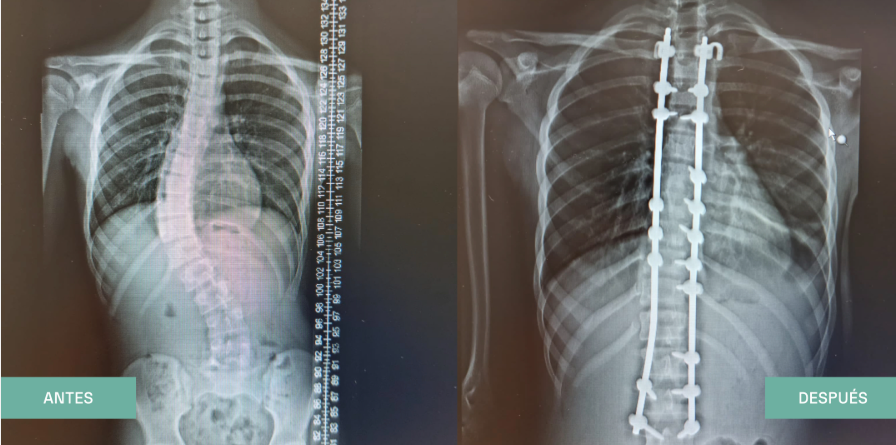

Хирургия позвоночника:

• Доктор Алехандро Пейро Гарсия — прошел двухлетнюю специализированную подготовку по детской хирургии позвоночника в Университете Калгари и Детской больнице Альберты в Канаде. Активно исследует методы лечения сколиоза и инновационные операции на позвоночнике, публикуя многочисленные статьи в международных журналах.

Рентген, показывающий до и после операции на позвоночнике у пациентов

до и после лечения сколиоза